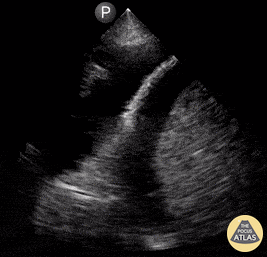

Pulmonary - Large Pleural Effusion

Patient presented to the emergency room reporting dyspnea. POCUS revealed presence of severe ascites and pleural effusion. Reyna Huerta Sanchez, MD @DraHuerta09